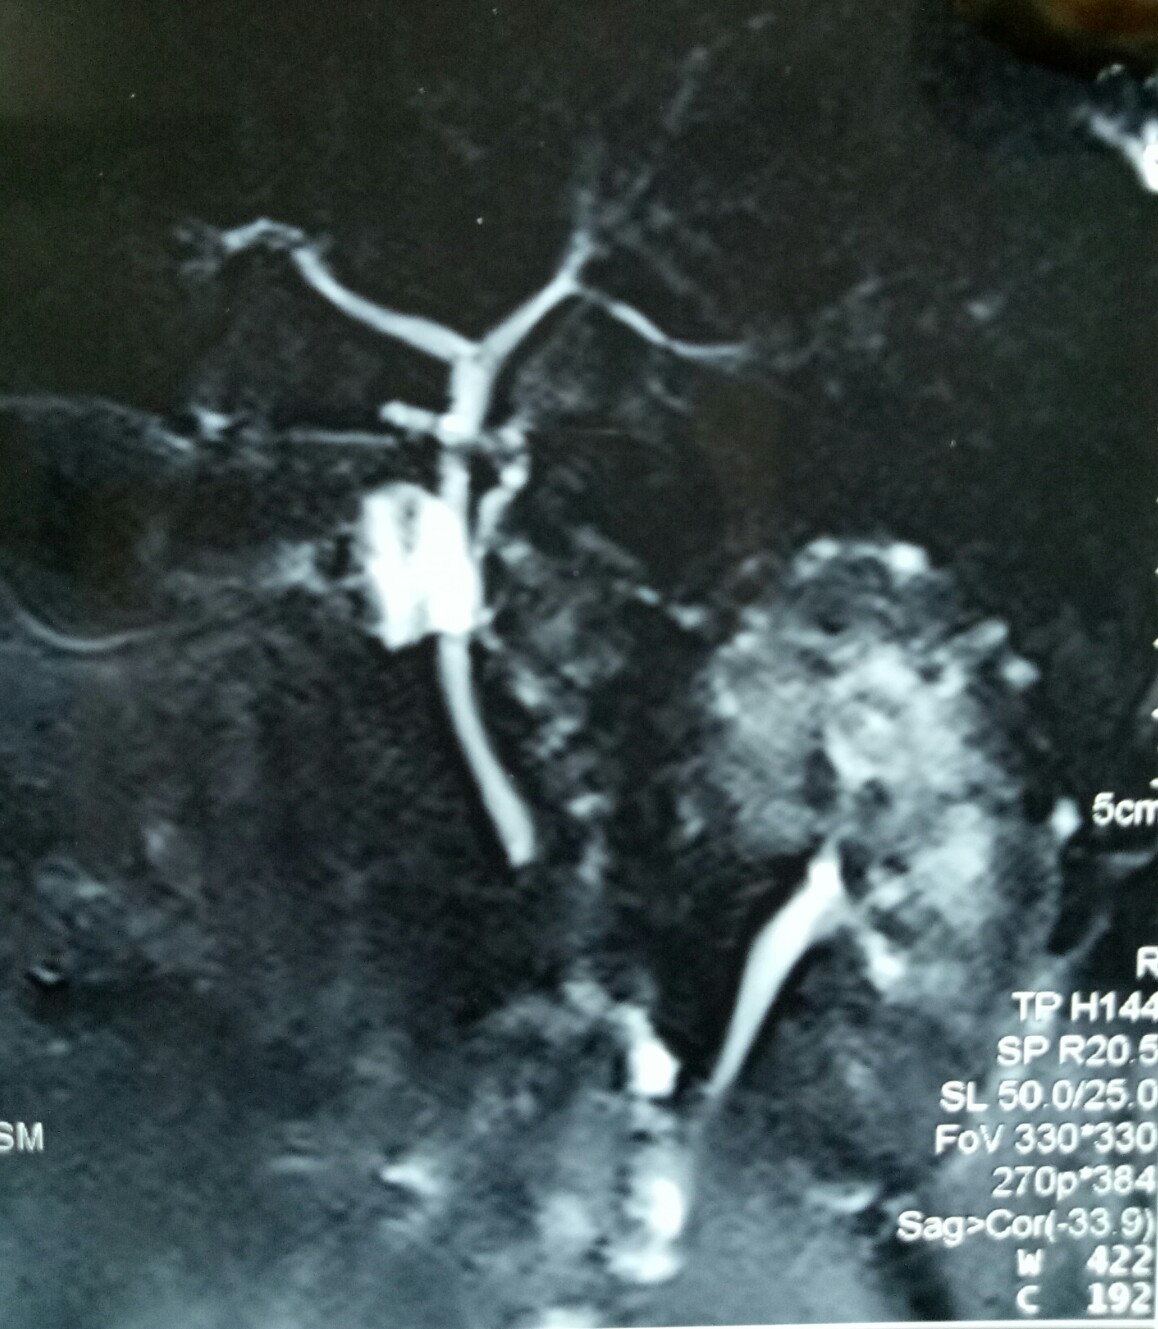

Another lap chole landing up in trouble. A young 30 year old male underwent a very difficult lap chole due to the frozen Calot’s triangle and a very thick-walled gall bladder. Postoperatively had a bile leak which was 200 cc on the first postoperative day and then continued to decrease in amount gradually drying up in 18 days. MRCP reported a small collection and a ? kink and narrowing at the site of cystic duct-CBD junction. the radiologist’s reported this as a cystic duct blow-out!